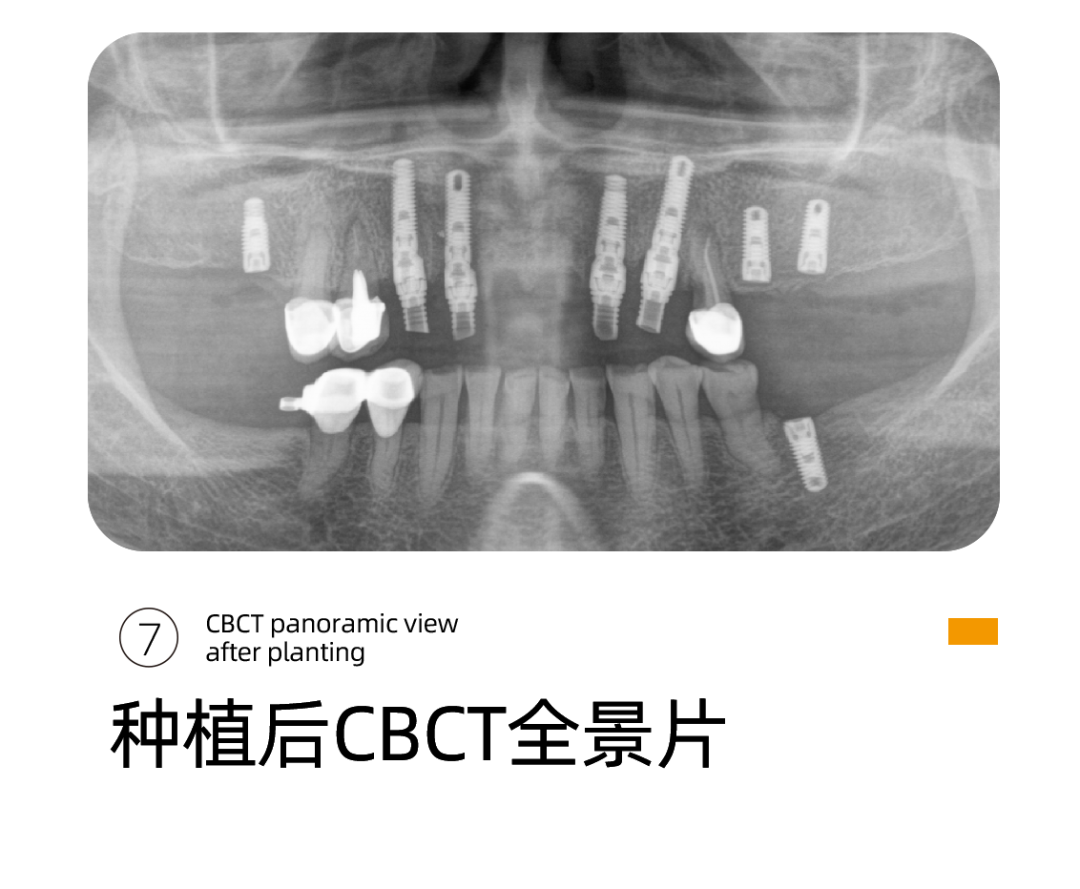

针对阿姨的情况,李雪松院长为阿姨指定全套的数字化种植方案。

其实就是借助Sirona CBCT全景影像信息和相关修复信息为基础,借助数字化专业种植设计软件进行术前诊断和种植方案规划。

通过数字化种植手术导向模板,将术前制订的种植方案准确应用于种植手术和即刻修复的全过程,实现以修复为导向的牙种植修复。

全数字化导板设计会依靠自身数字化的精确定位和微创特点,大大减少失误操作,提高种植手术的精准度。

精准、高效、微创性瞬间提升,伤口更小,出血更少,恢复的更快更好。